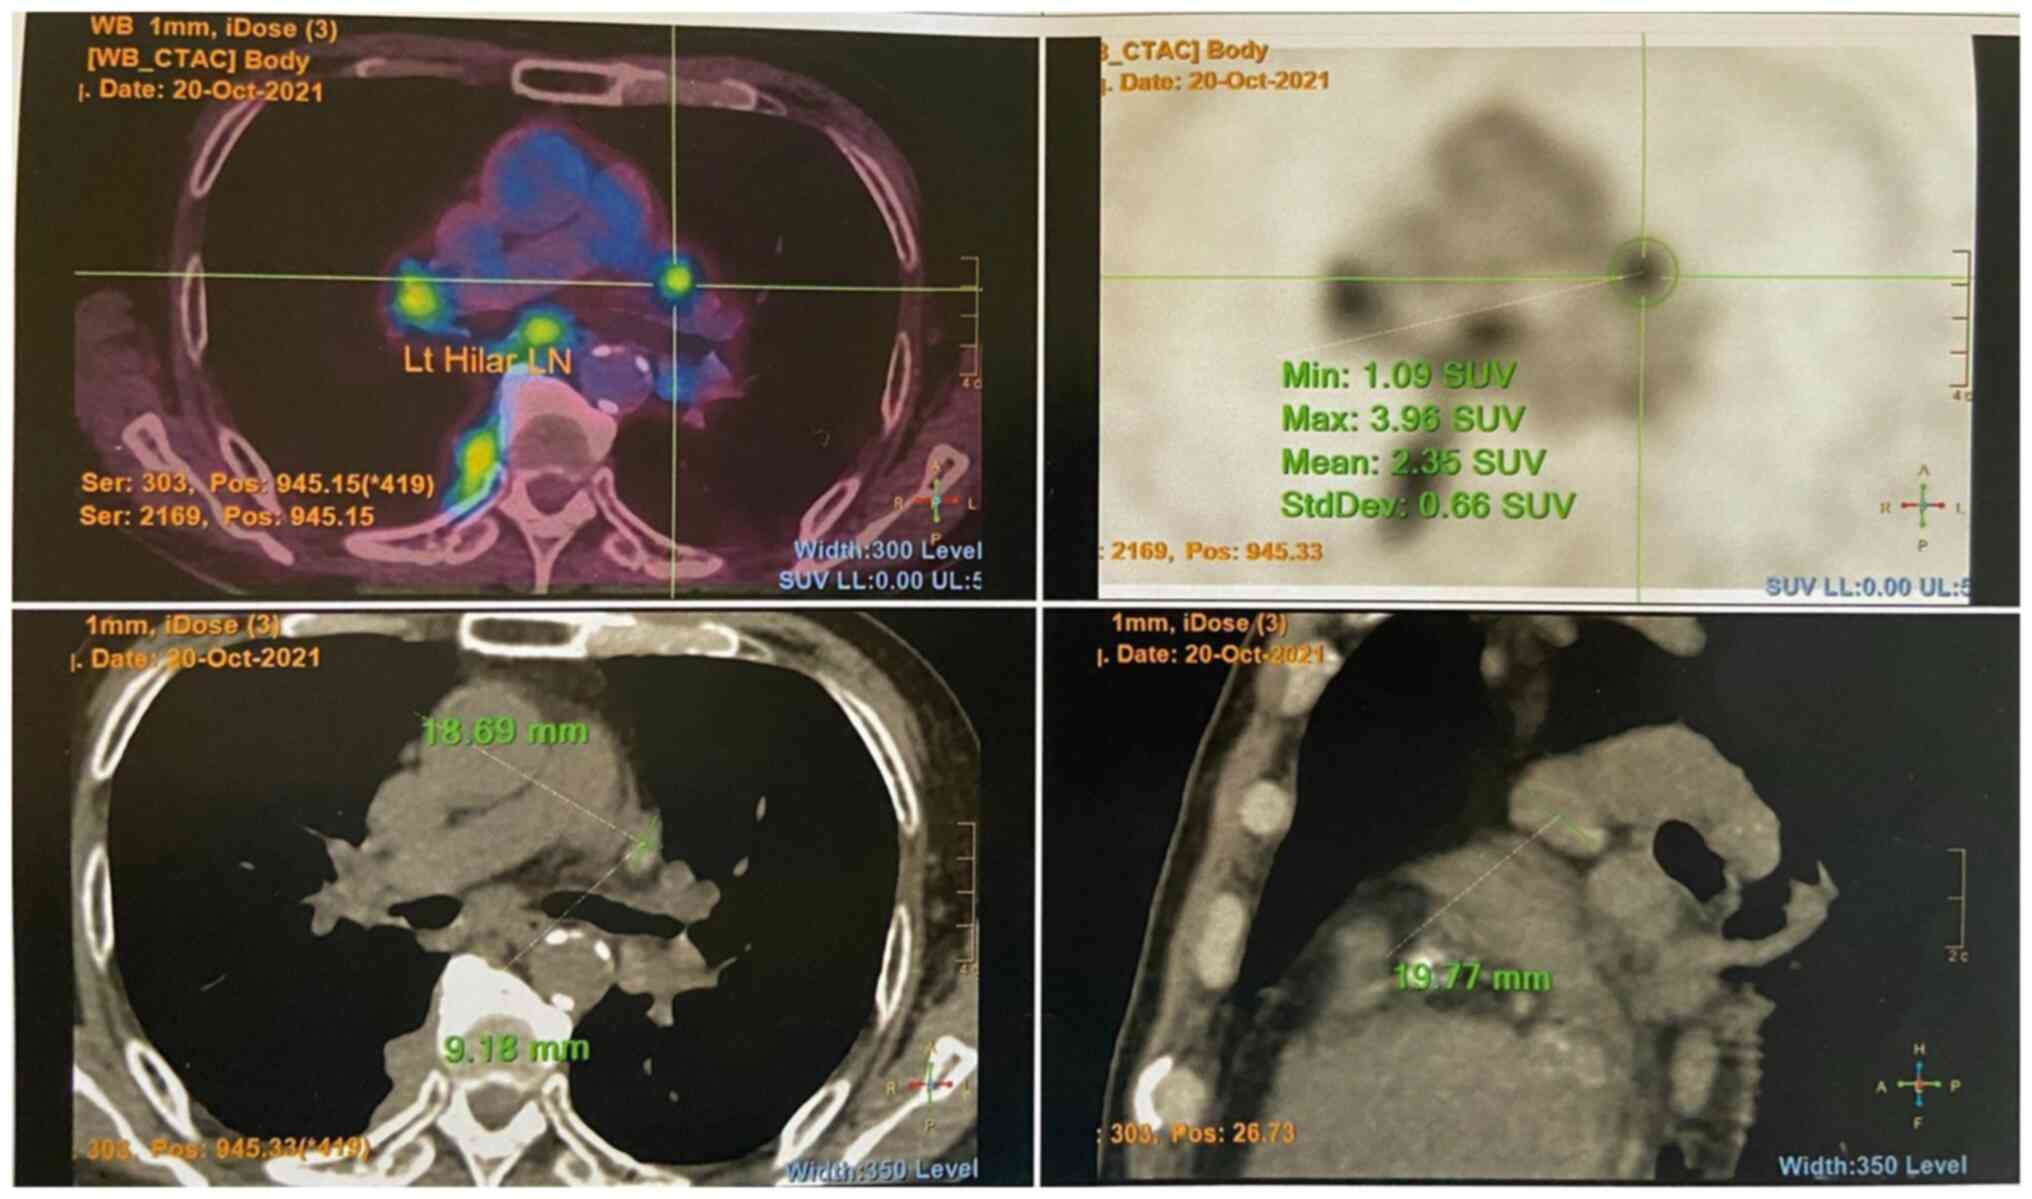

The levels of tumor markers, including alpha fetal protein (3 µg/l), prostate-specific antigen (<0.03 µg/l) and carcinoembryonic antigen (1.9 µg/l) were withiun normal range. He had an increased eosinophil count (1.9x109/l; reference range, 0.0-0.5x109/l) and an erythrocyte sedimentation rate of 119 mm/h (reference range, <32 mm/h). Autoimmune markers including antinuclear, antineutrophil cytoplasmic, Sjögren syndrome-related antigen A/Ro, Sjögren syndrome-related antigen B/La, double-stranded DNA, ribonucleoprotein and Smith antibodies were all negative. His serum IgG4 count was increased (2,269 mg/dl; reference range, 9-146 mg/dl). A positron emission tomography-computed tomography scan revealed multiple fludeoxyglucose F18 (FDG)-avid enlarged mediastinal, hilar, (Fig. 1) and submandibular lymph nodes, as well as an FDG-avid right parotid gland nodule. An FDG-avid nodular thickening of the right posterior pleura was also noted at the T9/10 level (Fig. 2).

Figure 1

PET/CT image illustrating multiple FDG-avid enlarged mediastinal and hilar lymph nodes. The top left image is a transverse cut fusion (PET/CT) image. The top right image is a transverse cut PET image. The bottom left image is a plain CT transverse cut image. The bottom right image is a plain CT sagittal cut image. PET/CT, positron emission tomography-computed tomography.